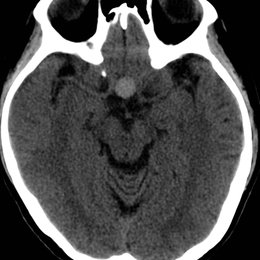

PREGUNTA 3 de 10

¿Cuál es el diagnóstico más probable de la siguiente imagen?

A)

quiste aracnoideo

B)

Quiste de la bolsa de Rathke

C)

craneofaringioma

D)

Silla turca vacía

E)

macroadenoma hipofisario